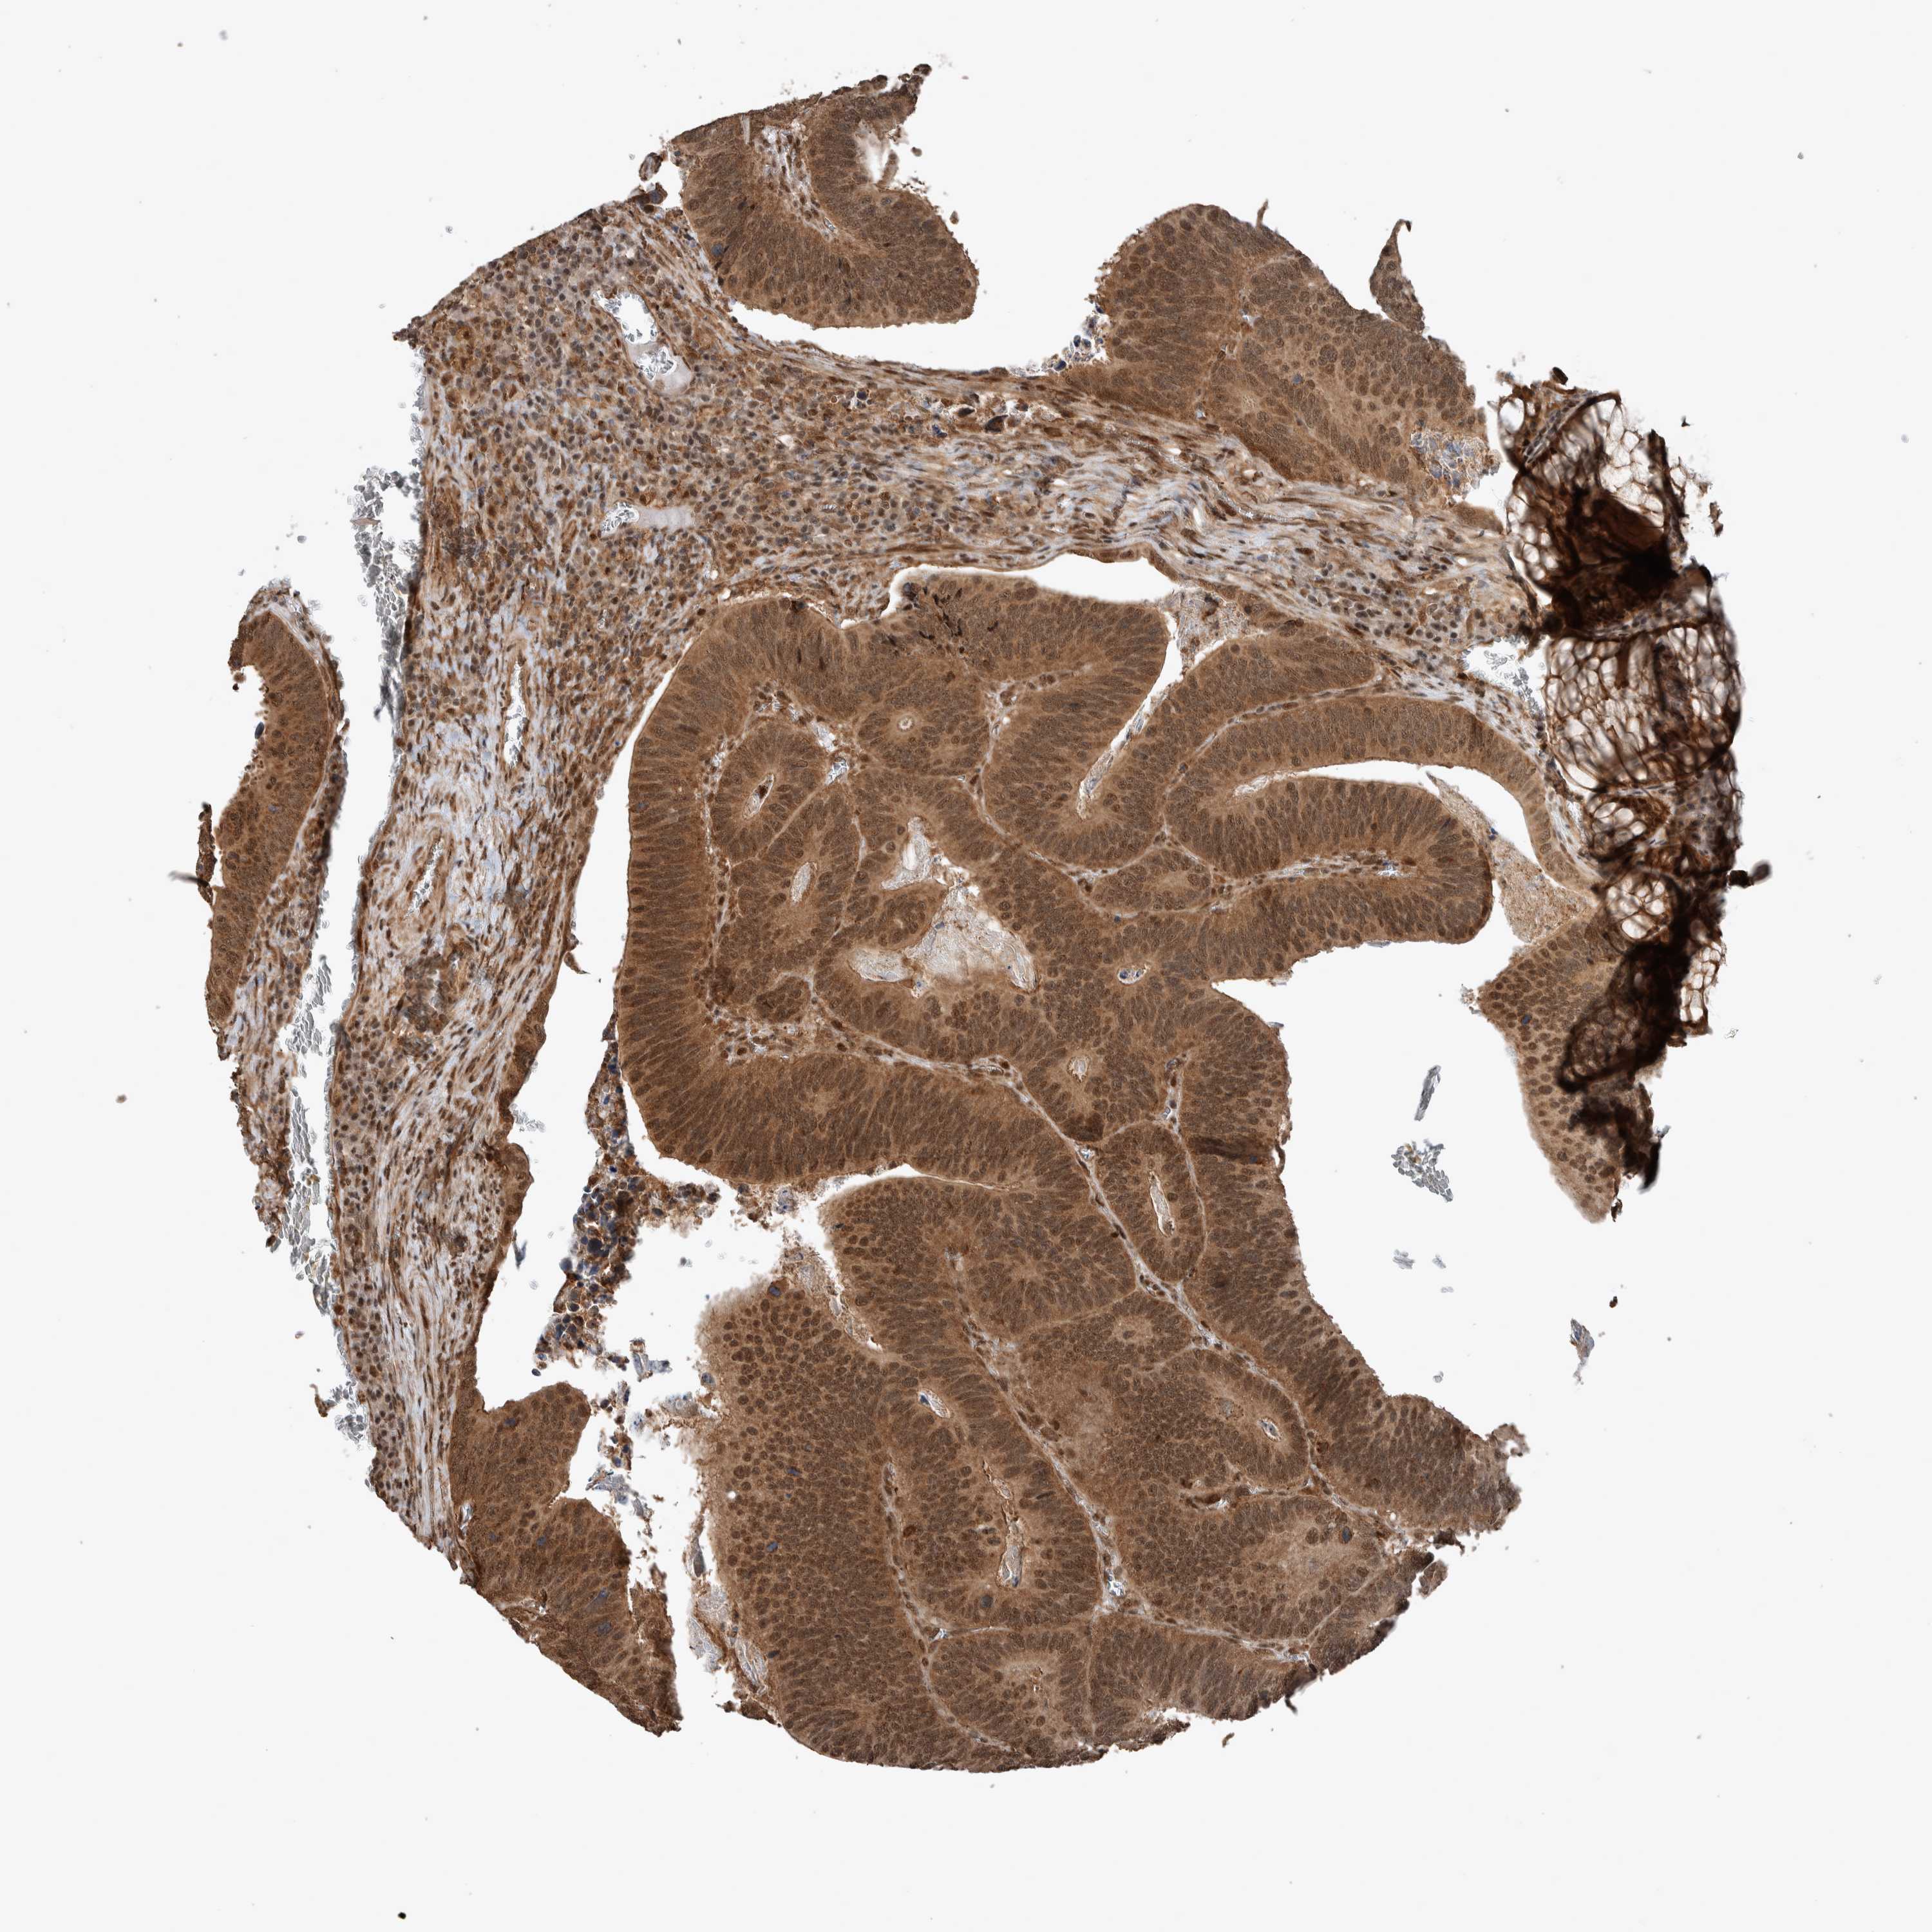

CANCER COLORECTAL CANCER Show tissue menu

Colorectal cancer

Human cancer

Colon adenocarcinoma